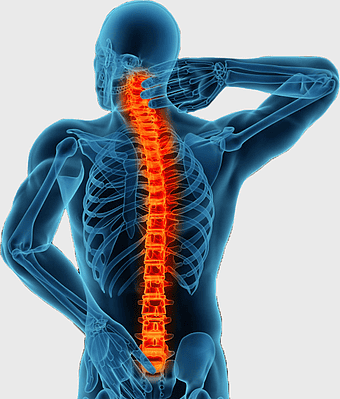

vertebral column anatomy, spinal cord health, cervical vertebrae structure, monochrome medical illustration, skeletal system diagram, human spine model, central nervous system function -

neck pain treatment, back pain relief, cervical spine anatomy, physical therapy exercises, spine health, musculoskeletal pain, medical imaging analysis -

vertebral column, spinal fusion, minimally invasive spine surgery, back pain, human anatomy, medical illustration, skeletal health -